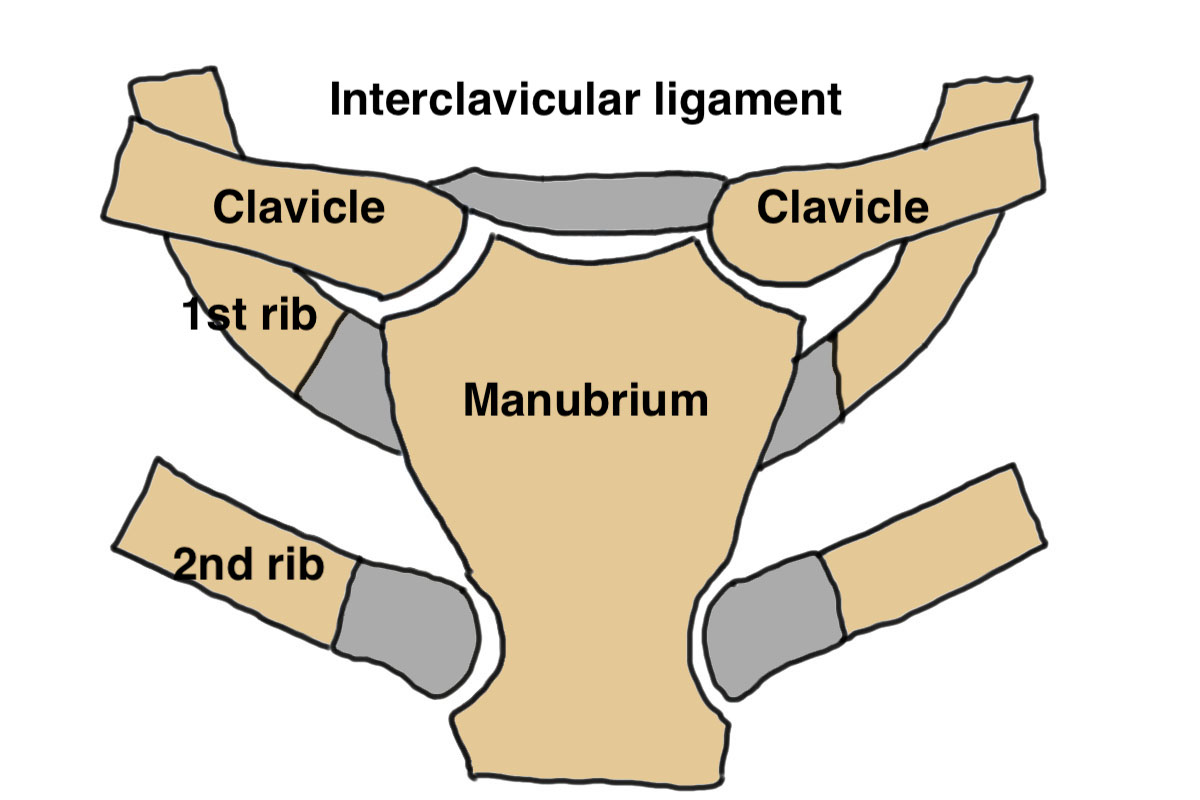

Anatomy

Medial clavicle physis is last to fuse aged 23 - 25

- can be medial clavicle physeal injury up to 25

Sternoclavicular joint

- synovial joint with a fibrocartilaginous disc

- only 50% of medial clavicle articulates with manubrium

- costoclavicular / interclavicular / sternoclavicular ligaments

Vascular

- brachiocephalic veins lie directly behind SCJ

- common carotid artery / subclavican artery / aortic arch / internal jugular vein very close